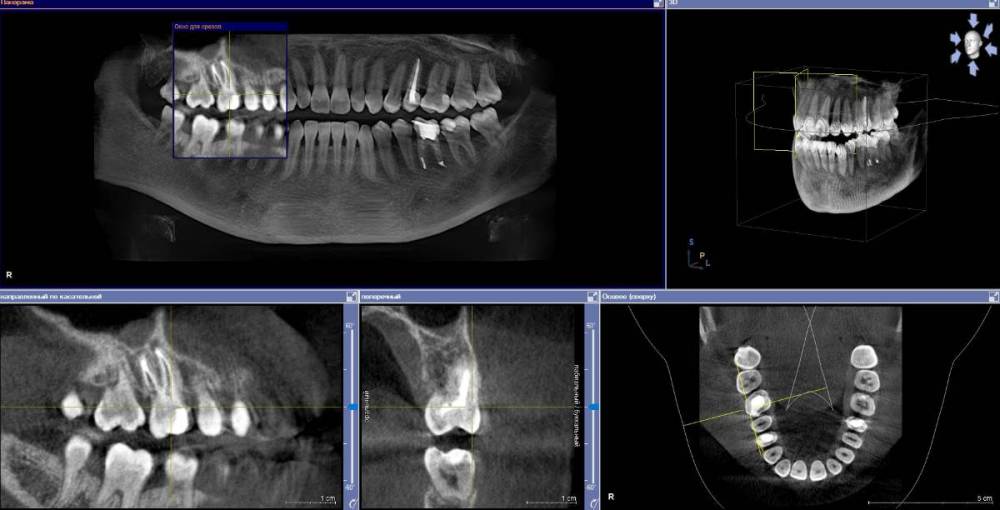

anishuma Опубликовано 1 сентября, 2021 Поделиться Опубликовано 1 сентября, 2021 (изменено) Здравствуйте, прошу помочь разобраться с моими КТ и направить для дальнейших действий. История такая: в 2018 году шестой зуб сверху справа был депульпирован. Долго сохранялись боли при нажатии, при жевании, зуб реагировал на холодной и горячее. Врач, который лечил, заверила что это постпломбировочные боли и скоро пройдет. Коронку побоялась ставить из-за этих болей. Затем примерно через год отлетел кусочек пломбы. Зуб восстановили для дальнейшей установки коронки. На данный момент есть ощутимая реакция на давление, при жевании, при чистки зубной щеткой. Зуб реагирует на холодное-горячее. Один врач сказал, что не видит показаний для перелечивания каналов. Другой врач настаивает на удалении зуба. Подскажите, пожалуйста, где истина, и возможно ли сохранить зуб. Изменено 1 сентября, 2021 пользователем anishuma Ссылка на комментарий

Bier Опубликовано 2 сентября, 2021 Поделиться Опубликовано 2 сентября, 2021 похоже что есть гранулема на корне 2 Ссылка на комментарий

St. Опубликовано 3 сентября, 2021 Поделиться Опубликовано 3 сентября, 2021 +1 к гранулеме. Я бы перелечивала каналы. Но нужно в процессе будет смотреть нет ли трещин в корне. Ссылка на комментарий